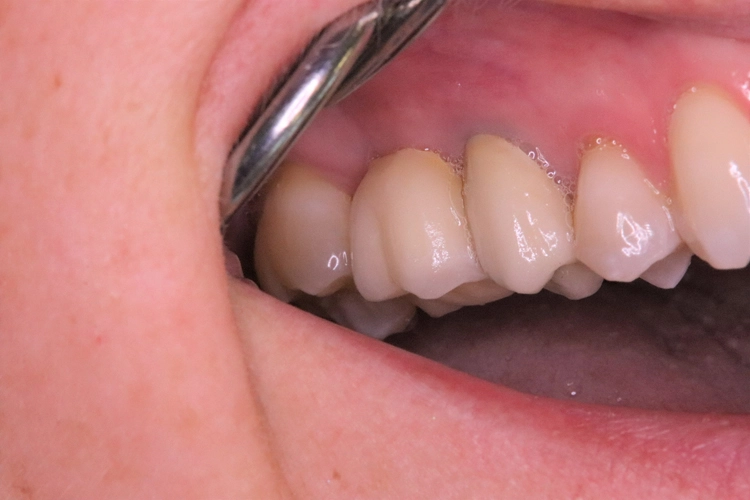

Kontrollbild und Röntgenkontrolle ein Jahr und ein Monat nach Socket/Ridge Preservation (Abb. 21 und 22). Der komplette Umbau zu Eigenknochen ist noch nicht abgeschlossen. Die Papillenregeneration zwischen 13/14 und 14/15 ist jedoch deutlich erkennbar.